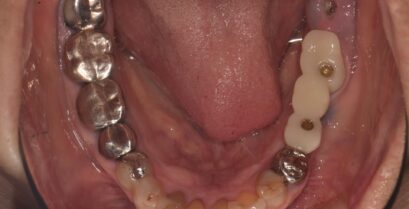

インプラントのメンテナンスを怠るのが危険な理由!

インプラントを検討中の人は、治療後のメンテナンスが重要という話を聞いたことがあるかと思います。インプラントは人工歯根を埋めて、上部構造を装着するまでに...